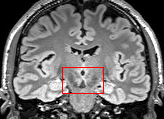

To test the impact of the iterative refinement on YODA’s translation quality, we compared regression and diffusion sampling on the RS data and present additional generation examples in Fig. 6. We observe that diffusion sampling visually resembles the appearance of the acquired images. Regression sampling preserves key anatomical features – the GM/WM boundary, WMHs (Fig. 4), the outline of the pallidum (Fig. 6) – but omits many high-frequency features. To investigate whether iterative refinement during diffusion sampling adds relevant and systematic medical information or only imitates acquisition noise, we performed ExpA sampling, i.e. averaging the output of several ( or ) diffusion trajectories. We observed a gradual loss of high-frequency details when increasing the (see also the supplementary video), indicating that the effect of the iterative refinement is non-systematic. For , the images are visually almost indistinguishable from the initial regression solution (see the supplementary video, and Fig.4 and 6). We directly compared the synthesis results of ExpA () and regression sampling quantitatively and found the differences to be minimal (SSIM: 99.73%, PSNR: 45.30 dB), i.e. diffusion sampling approaches the initial regression solution for a high . The quantitative analysis of the image quality (Tab. 1) showed that diffusion sampling impairs the assessed SSIM and PSNR in comparison to regression sampling for both the in- and external test sets, which we attribute to noise generation (Sec. 3.1). In turn, ExpA averages improved both metrics and, for , performed mostly on par with the regression solution in both test sets in terms of SSIM, while the PSNR in the RS was slightly increased (Tab. 1). However, we observed that ExpA sampling YODA improves the replication of systematic 3D low-frequency image intensity drifts (bias fields) due to the 3D synchronization in 2.5D diffusion sampling. Yet, this apparent advantage did not generalize to the external MBB dataset, as bias fields are MR protocol-specific.

To assess the suitability of YODA-generated images for WMH detection independent of segmentation tools, we also calculated the CNR (15) of WMHs. This confirmed that the contrast of WMHs is preserved in the regression images, whereas we noted slightly reduced WMH contrast for diffusion and ExpA-sampled images (Tab. 1).

On the RS data (Tab. 1), regression sampling of YODA significantly outperformed all competing methods both w.r.t. the image quality and – except the ALVR for MADM – downstream WMH segmentation, whereas the DB of Choo et al. [31] achieved an higher WMH CNR.

When analyzing the RS synthesis results (Fig. 4), we noted that most reference methods strive to imitate realistic images, but several artifacts can be observed such as hallucinated WMHs (SynDiff) and salt-and-pepper noise (SynDiff, I2I-Mamba, ResViT).